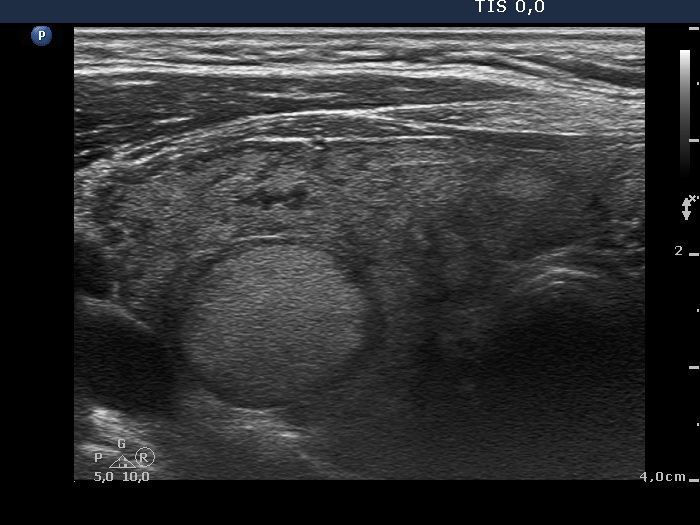

Ultrasonography. The thyroid was minimally-moderately hypoechogenic and was composed of multiple discrete areas. The right lobe presented a micronodular pattern and had a hyperechoic lesion which was suspicious being a pathological nodule. The left lobe contained multiple nodules, one of them located in the middle part was moderately hypoechogenic.

It is worth to compare the thyroid lobes: the right did not prove to be containing nodule is pathological sense, the large hyperechoic lesion was the only intact part which was not or less infiltrated by the thyroid. On the other hand, the left lobe had multiple lesions.